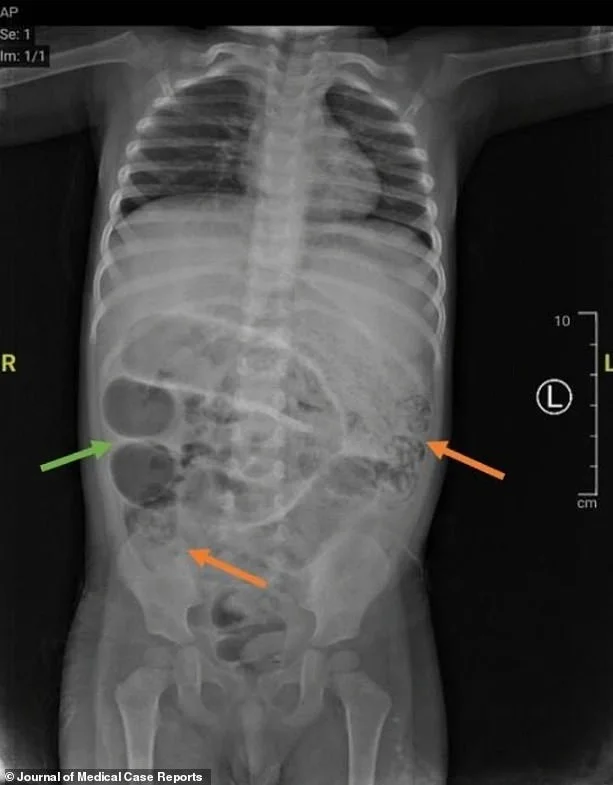

Surgeons performed a laparotomy — an incision into the abdomen — and found worms blocking three sections of the small intestine. The parasites were removed and sent to the lab for analysis.

This type of roundworm, known as ascaris, can grow up to 35 centimeters in length and live in the human intestine.